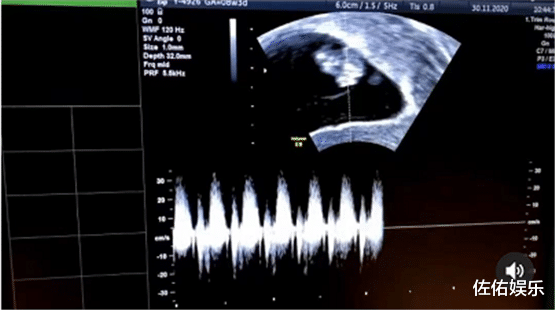

似乎难掩心中的喜悦 , 杨洛婷还分享了小宝宝的B超照 , 可以看得出来小朋友特别的好动 , 而且已经怀孕数月 , 并且属于高龄产妇的她 , 还和老公孩子一起 , 在空旷的地方蹦蹦跳跳的打闹着 , 画面特别的温馨幸福 。